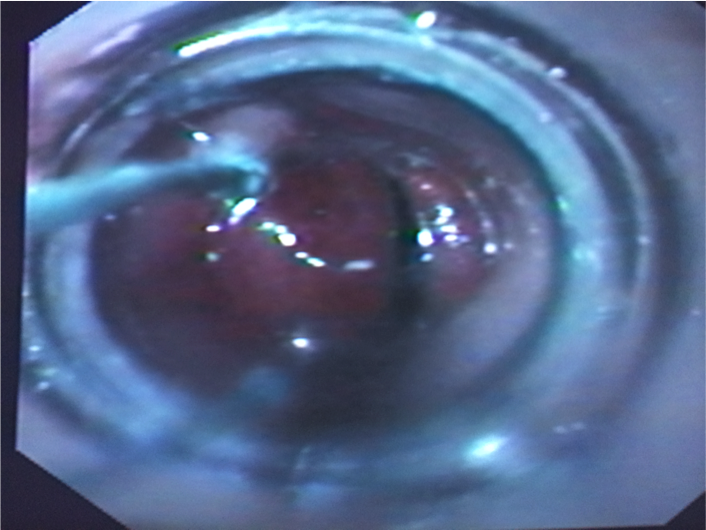

Figure 1 Rubber band ligator applied around a pile column by a video colonoscope using the forward view.